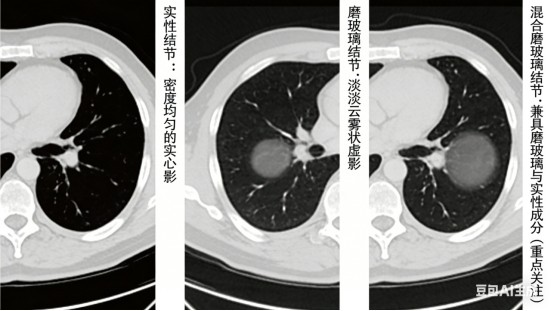

3. 看类型(根据密度区分)

·实性结节:密度均匀的实心影。

·磨玻璃结节:像一片淡淡云雾状的虚影。

·混合磨玻璃结节:兼有磨玻璃和实性成分,需重点关注其变化。